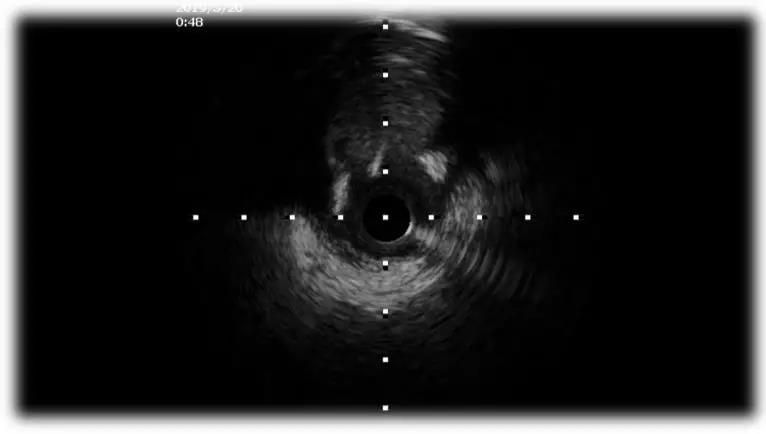

IVUS实时指导寻找LAD入口

2、IVUS实时指导寻找闭塞入口;

3、XT系列导丝引导;

4、遇上阻力,升级Gaia或CP系列;

5、平行导丝技术;

6、ADR;

7、IVUS评估和优化支架植入。